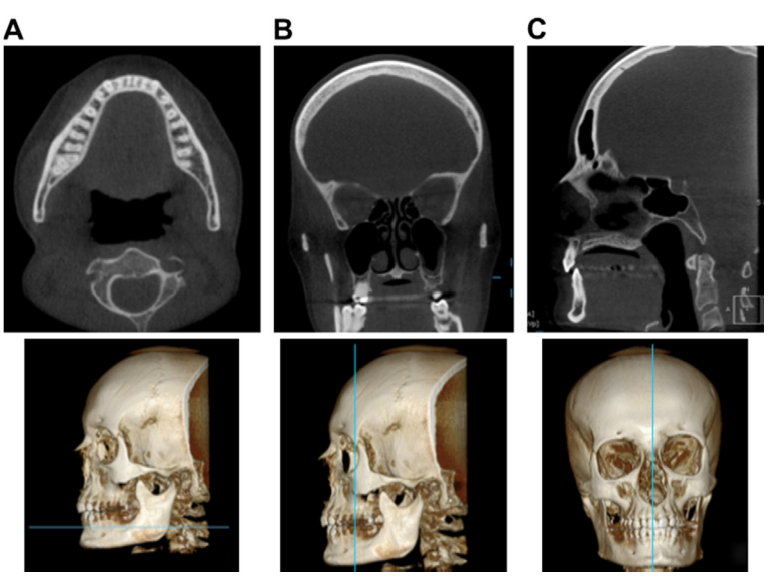

Sagittal, axial, coronal

What is CBCT FoV and how can it change?

A

Visible Field of View

• Can be adjustable

• Full FoV = nearly full skull (used for ortho)

• Medium / standard = both arches and TMJ

• Small FoV = one arch or quadrant

Want to limit the field size to the smallest volume that can accomodate the region of interest